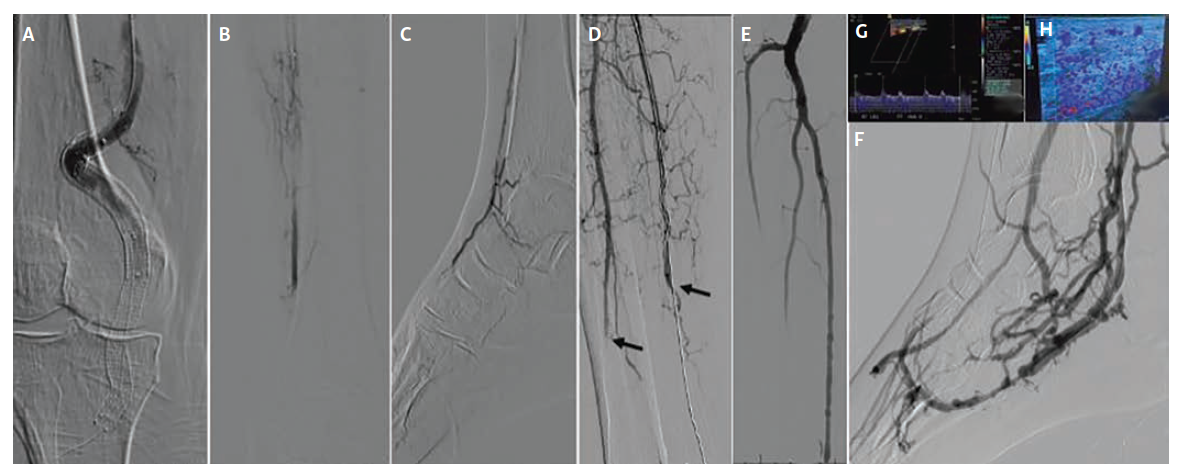

The first patient, a 65-year-old woman with Rutherford class IIb acute-on-chronic limb ischemia (Figure 1), developed abrupt superficial femoral artery (SFA)–popliteal–ATA thrombosis within 1 day of revascularization; DVA was undertaken within 36 hours after overnight catheter-directed thrombolysis failed to restore durable runoff. Baseline anatomy (after thrombolytic therapy) showed chronic total occlusion of the stented SFA, a chronic total occlusion of the PTA with no reconstitution, and single-vessel ATA runoff with severe dorsalis pedis disease and occlusion of the pedal arch.

Before proceeding with venous arterialization, inflow was optimized using femoropopliteal atherectomy, angioplasty, and stent placement across the SFA–popliteal segment. Because the ATA was the only patent vessel supplying the foot, it was selected for the initial DVA creation. Access was obtained via the dorsalis pedis vein. An Outback Elite re-entry catheter (Cordis) was used to cross back into the ATA from the venous system. Balloon angioplasty was performed to establish the arterial–venous connection, and a Viabahn 5 mm x 100 mm stent graft (Gore) was deployed across the anastomosis, followed by additional balloon angioplasty of the ATA–venous loop. While technically successful,

his approach effectively sacrificed the patient’s only remaining arterial runoff, making the limb more vulnerable despite good angiographic results.

Twelve days later, the procedure was revised to a PTA-based DVA in an effort to improve venous arch perfusion and redirect flow to the foot. Angiography at 3 months showed maintained brisk flow, and clinic exams documented strong DVA signals. The patient subsequently underwent TMA due to continued clinical deterioration and absent pedal signals; a later below-knee amputation occurred at an outside hospital, but no further clinical details regarding this secondary event are available.